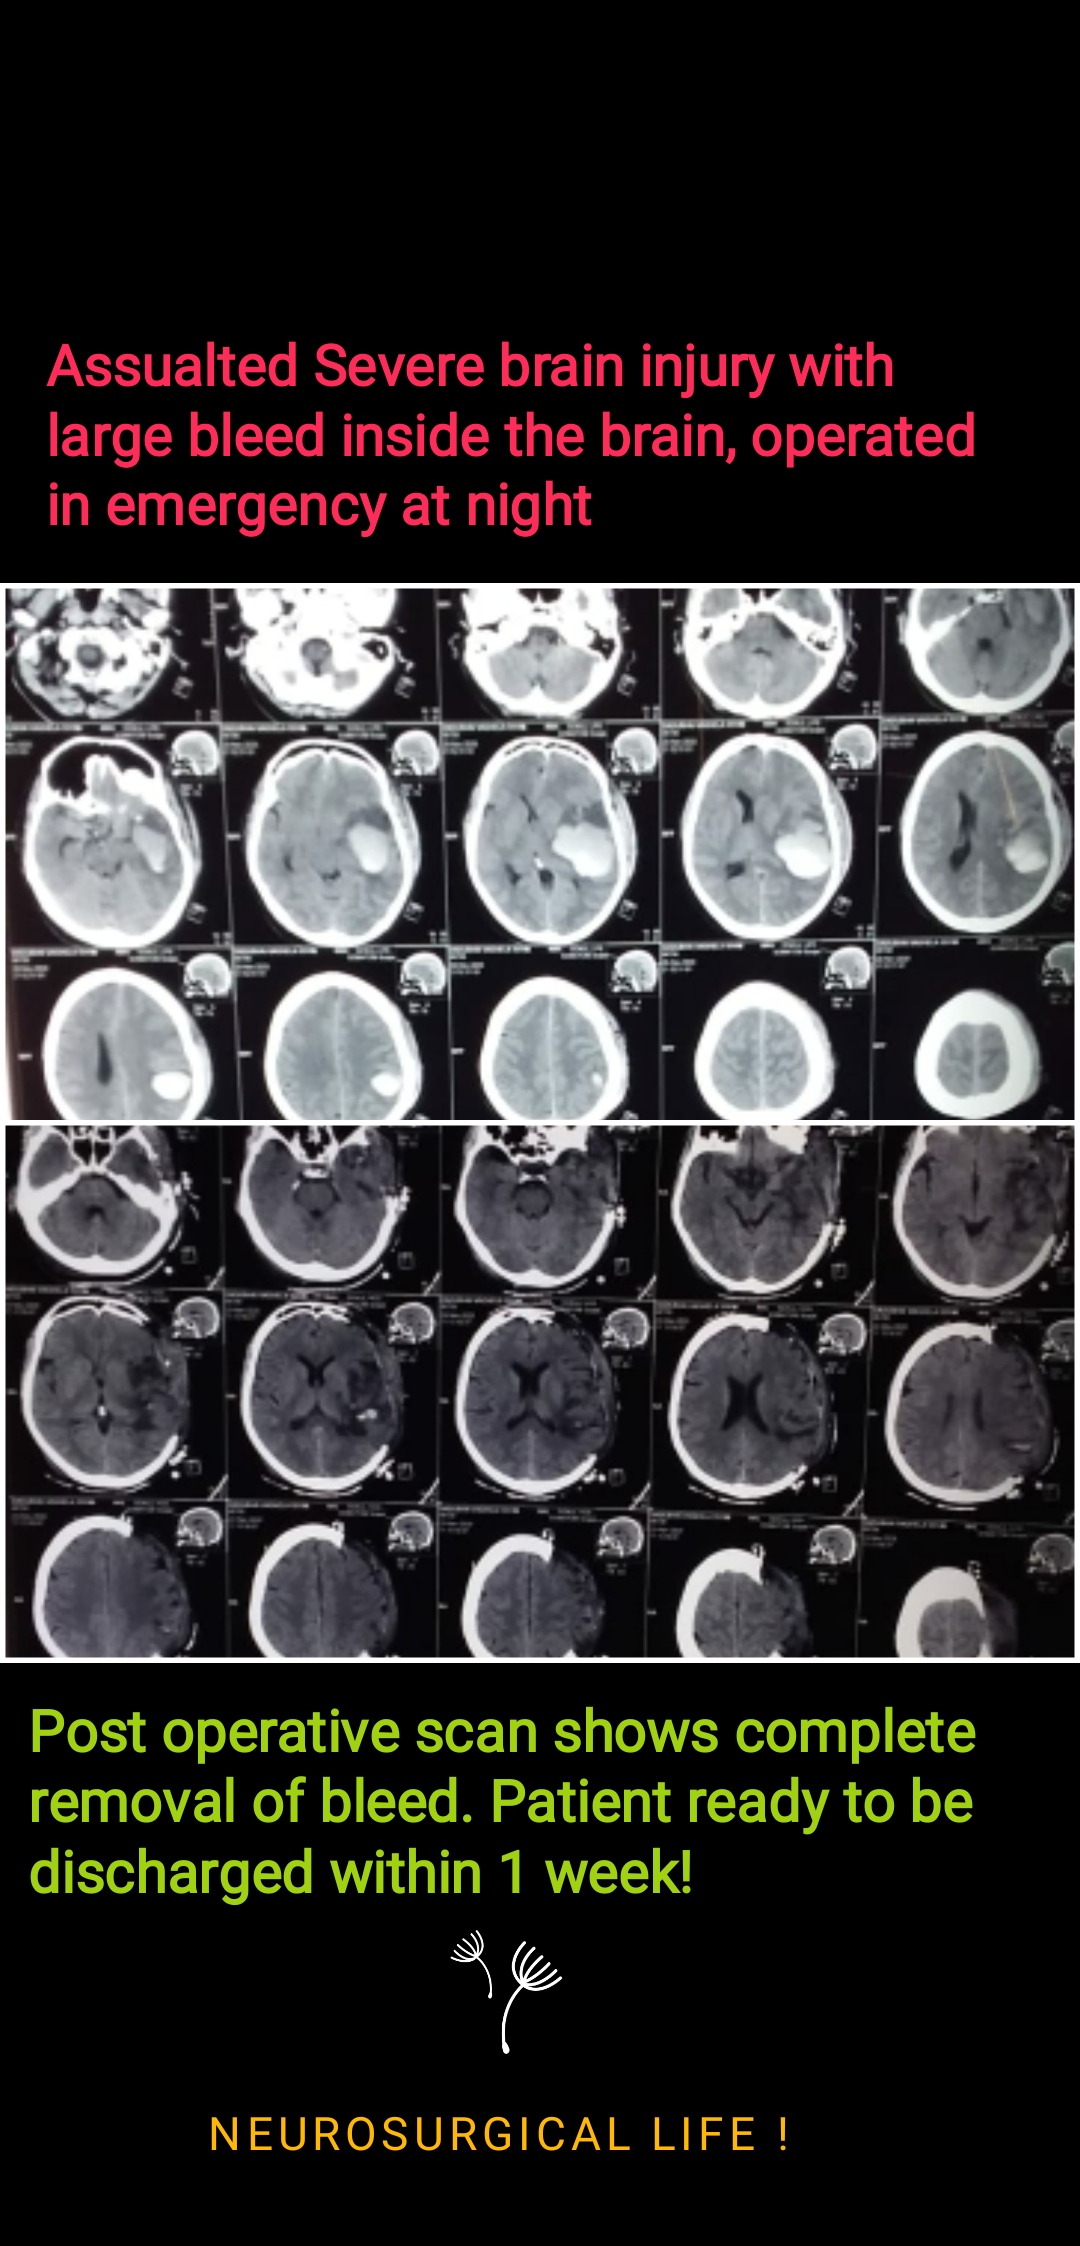

Head Injury

All kinds of trauma handling with utmost care